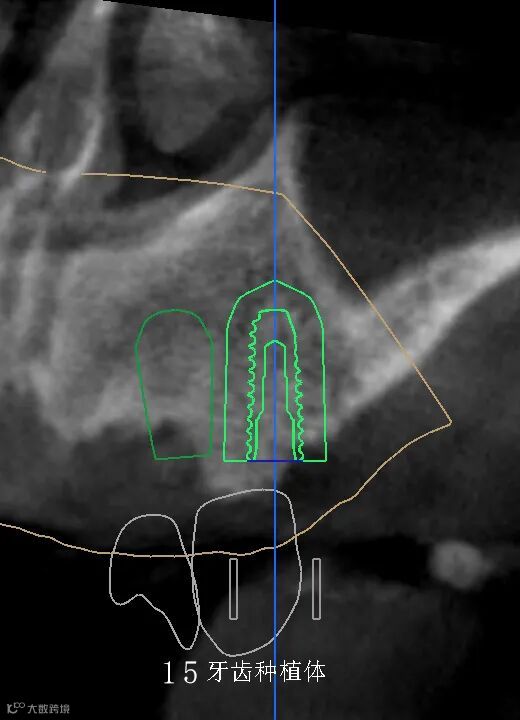

数字化种植手术规划与导板设计

精准——术前精确设计,术中精准控制,避免损伤重要的解剖结构,实现安全种植,以美学修复为导向,为永久修复牙位设计更理想、美观。